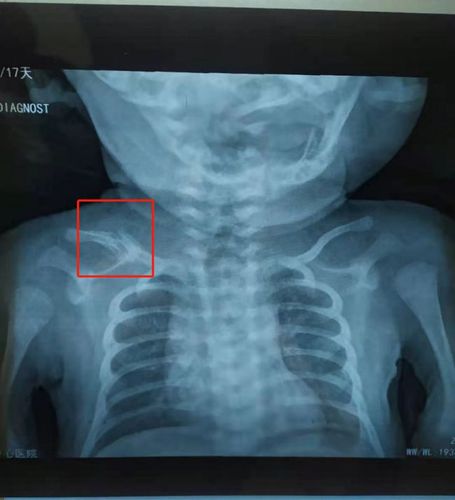

锁骨骨折错位,锁骨骨折错位图片

锁骨骨折错位图片

新生儿锁骨骨折

锁骨骨折x光图片